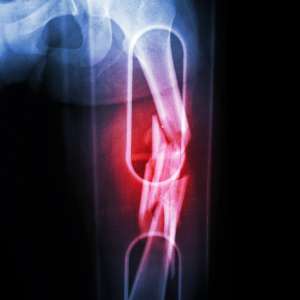

Malunion and Non-union:

- Sometimes fractures can go on to a malunion (heal in a deformed position) or non-union (fail to heal). These need a holistic approach to treatment to ensure all factors that may have resulted in the malunion or non-union are optimised and infection has been excluded.

Limb Deformity:

- Limb deformities may develop after injuries or illnesses, leading to challenges with mobility and quality of life. A holistic approach to these cases is essential often needing a multidisciplinary approach to ensure the health of the patient is optimised, along with any specific surgical and non-surgical managements to the specific bone. The aim of any treatment is to help regain function and reduce pain.